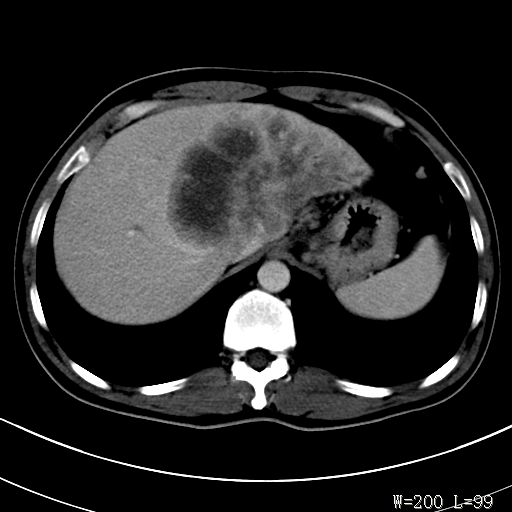

标题: CT27340:肝脏病变?

男,45岁,发热、乏力半月,午后为主。

对比剂快进快出,首先考虑肝左叶巨块型肝癌。

其次,感染性病变,如肝脓疡不排除。

蜂巢,肝脓肿

蜂巢状,支持!肝脓肿的诊断。

考虑肝脓肿,请查血象

考虑肝内胆管细胞癌。